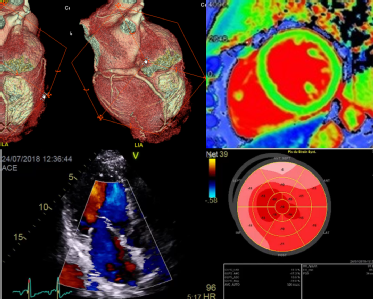

vertical long axis (corresponding to the echocardiographic apical 2-chamber plane).planes parallel to that plane containing both the long axis and the "horizontal" line drawn at the mid ventricular level between the center of the left ventricle and the transition between the diaphragmatic and free wall of the right ventricle 6.horizontal long axis view (corresponding to the echocardiographic apical 4-chamber plane).short axis view (corresponding to the echocardiographic parasternal short axis plane).The planes are defined in reference to the long axis of the left ventricle, which is the line that connects the ventricular apex to the center of the mitral valve 4-6: Cardiac imaging planes are standard orientations for displaying the heart on MRI, CT, SPECT, and PET, similar to those used in echocardiography.